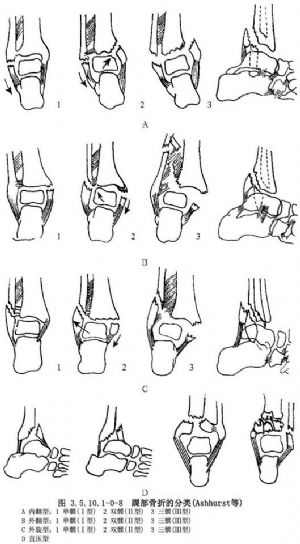

踝部骨折根據受傷機制、暴力方向大小,傷及範圍不同,產生畸形與移位亦各不同,處理各有所選擇。

根據受傷機制及病理解剖,可分類如下(Ashhurst及Bromer,1922):

(1)內翻骨折:①1°外踝骨折或外側韌帶傷(單髁)。②2°內踝也有骨折,內側半脫位(雙髁)。③3°後踝也骨折,內側脫位(三髁)。

(2)外翻骨折:①1°內踝橫折。②2°外踝同時斜折或脛腓韌帶斷裂、下脛腓分離或腓骨下端骨折,伴半脫位。③3°後踝也骨折。

(3)外旋骨折:①1°外踝斜或螺旋骨折。②2°內踝同時撕脫骨折。③3°後踝也骨折,外後脫位。

(4)直壓型骨折:足跟着地,足背屈,引致脛骨前緣骨折,距骨間前脫位,或脛骨及兩踝粉碎骨折(圖3.5.10.1-0-8)。

Weber(1966)則根據腓骨骨折水平區分踝部骨折分三類,逐類加重。此有助於正確認識骨與韌帶損傷,即腓骨骨折越高,脛腓韌帶損傷越重,踝穴不穩的危險性越大。

(1)Ⅰ型:骨折在踝關節水平或以下,韌帶很少損傷。①腓骨踝關節下橫行撕脫骨折,或相應的外側副韌帶斷裂。②內踝。完整或剪力骨折,折線斜行或脛骨邊緣壓縮骨折。③脛骨後緣一般完整,偶有後折塊與內踝折塊相連。④脛腓韌帶聯合體完整。

(2)Ⅱ型:骨折通過聯合韌帶部分,伴有關節不同程度損傷。①腓骨螺旋形骨折。②內踝撕脫骨折或相應的三角韌帶斷裂。③脛骨後緣完整或撕脫骨折的外側骨折塊。④脛腓韌帶聯合體骨間膜完整性依據折線位置。如在踝關節水平以下開始的螺旋骨折,前聯合韌帶完整。如骨折在踝關節水平開始,前聯合韌帶撕裂及相應的聯合韌帶從脛骨或腓骨附着點撕裂。

(3)Ⅲ型:包括聯合韌帶以上腓骨損傷,高達腓骨幹,伴內踝及韌帶傷。①腓骨在聯合韌帶與腓骨頭間骨折,或相應的脛腓脫位。②內踝橫形撕脫骨折,或相應的三角韌帶斷裂。③脛骨內緣外側折塊,後聯合韌帶撕脫骨折。④脛腓韌帶複合體有斷裂,骨間膜也斷裂。聯合韌帶本身斷裂,或骨的附着點撕脫(圖3.5.10.1-0-9)。

分類的目的是用以指導治療,抵消骨折應力,使不再變位。根據受傷時足的姿勢和致傷方向的分類,並不完全符合臨牀所見,且未表明下脛腓分離。依據腓骨骨折部位與下脛腓聯合體的關係改變分類,對損傷的診治又有進展。Weber與Hausen(1950)更結合此兩種分類,分爲三型,可更好地指導診治,尤其是不穩定型損傷。

(1)Ⅰ型(內翻內收型):踝部極度內翻,外側副韌帶先牽拉外踝,腓骨在聯合韌帶水平以下撕脫骨折。暴力持續,距骨撞擊內踝,發生斜行骨折。

(2)Ⅱ型:又分爲二亞型:①外翻外展型踝極度外翻,內側副韌帶牽拉內踝,發生內踝撕脫骨折。暴力若持續,腓骨在聯合韌帶水平斜折,同時後踝也有骨折。②內翻外旋型首先外踝斜折,由聯合韌帶水平起,向上伸延,形成粉碎骨折。後踝骨折,最後撕脫內踝,但下脛腓關節不分離。

(3)Ⅲ型(外翻外旋型):內踝先發生撕脫骨折,進一步下脛腓關節分離。腓骨在聯合韌帶水平上斜折或粉碎骨折,有時骨折發生在高位頸部(圖3.5.10.1-0-10)。